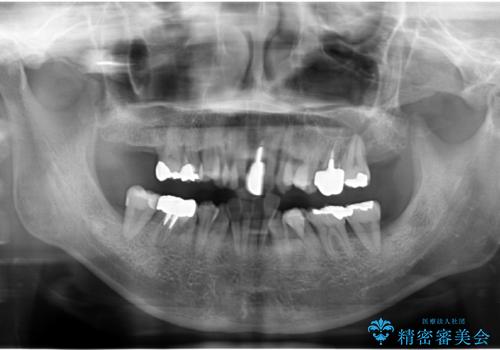

- 重度の歯周病に罹患しており、他院で「多数の歯を抜歯したのち、入れ歯を入れるしかない。」と言われ、入れ歯以外の方法がないか相談のため来院されました。

重度の歯周病で多数の歯を残せない問題、歯並び・噛み合わせの問題、欠損の問題、と多数の大きな問題が認められました。

このままの歯並びでは仮にインプラントを埋入したとしても歯ブラシがしづらく、また歯周病の問題が再発しやすい、と判断し矯正治療を行ったのちに歯周病治療、インプラント治療を行っていく治療計画としました。

インプラント治療に加え、歯周病に対しての再生治療や歯周ポケットの除去を行う歯周外科、矯正治療、と必要な治療は多岐に渡りましたが、最終的に安定した噛み合わせを得られたとともに、清掃のしやすい口腔内環境を確立できました。